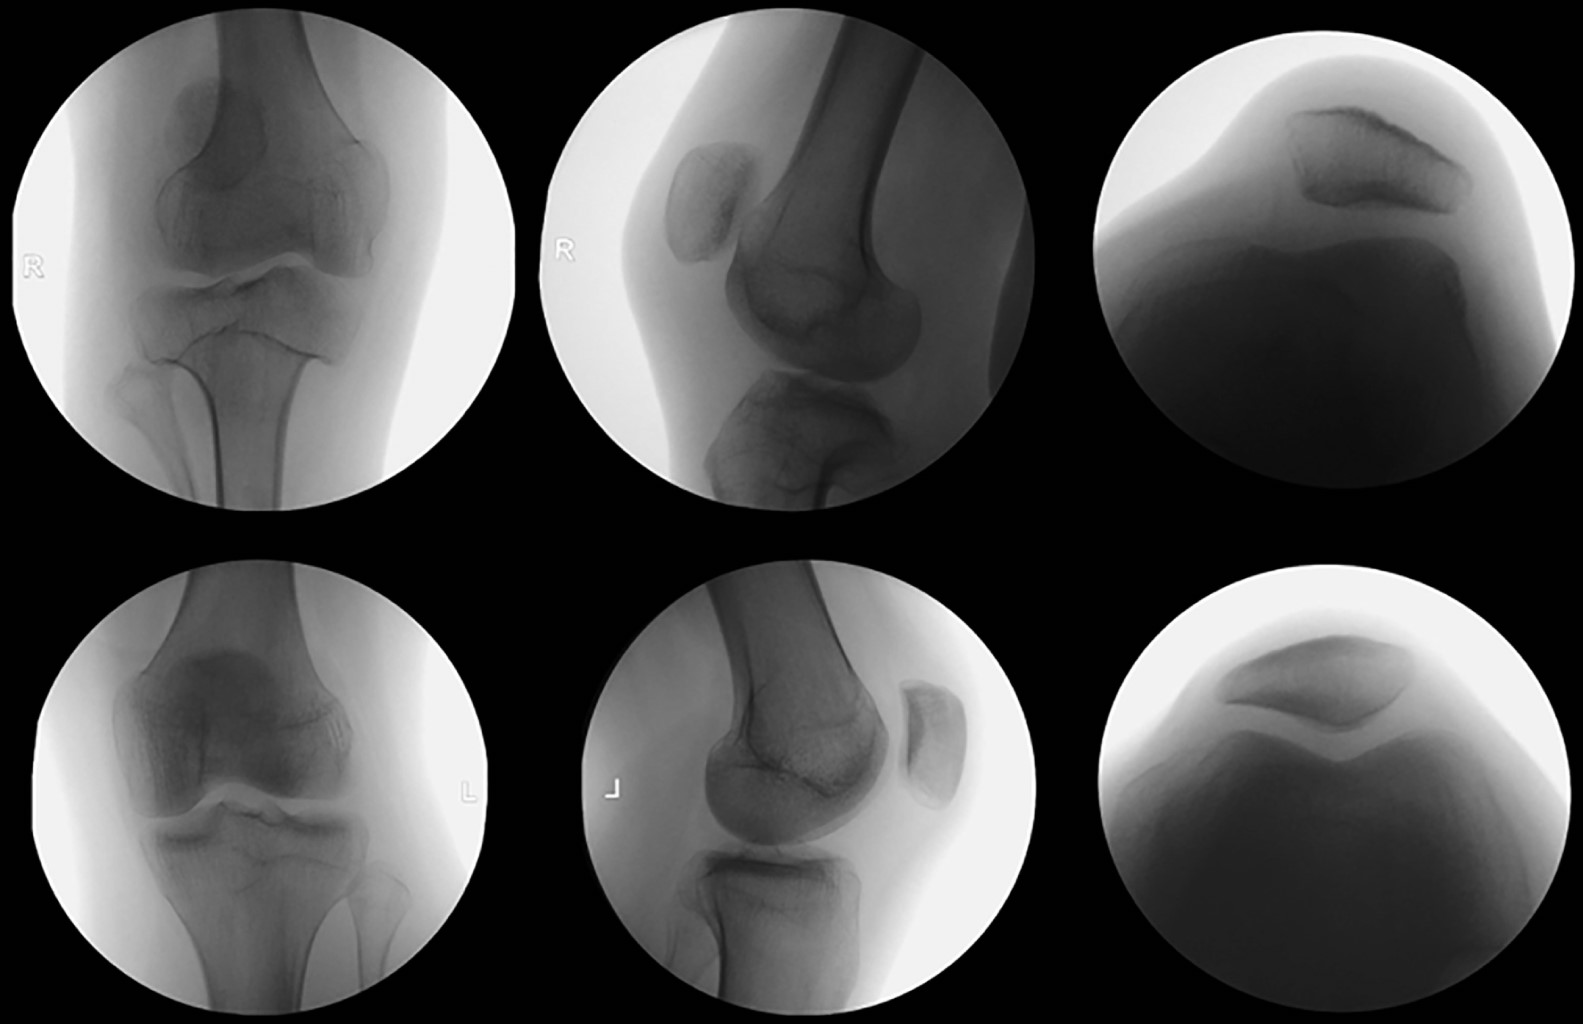

La inestabilidad patelofemoral es una condición multifactorial que abarca un espectro de manifestaciones que van desde subluxaciones hasta luxaciones completas de la rótula. Desde el punto de vista etiológico, puede originarse a partir de diversas anomalías anatómicas, incluyendo la alineación de las extremidades, la morfología ósea de la articulación patelofemoral y la integridad de los estabilizadores estáticos y dinámicos. Los pacientes con amputación por debajo de la rodilla tienen un mayor riesgo de experimentar inestabilidad patelofemoral. Este informe describe un caso que involucra a un paciente con inestabilidad patelofemoral y una amputación transtibial, tratado de manera efectiva con realineación distal y estabilización patelar lograda mediante la reconstrucción del complejo patelofemoral medial (CPFM).

Figura 3